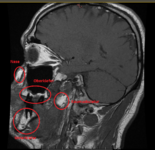

Ich habe auf Toxcenter endlich (aus dummen Zufall) die Bilder gefunden wo man Kieferaufnahmen erkennt, bewertet wurden, sowie auch Hirnaufnahmen.

Jetzt kann ich endlich versuchen mein OPG zu deuten. Ferner habe ich meinen Zahnarzt darum gebeten mir eine Überweisung zur Radiologie zu geben damit ich ein Vergleich des Kiefers vor und nach der Sanierung habe. Und auch um die aktuelle Belastung mit den Bildern und Dokumentationen von Toxcenter bewerten zu können. Oder es zumindest zu versuchen. Obs stimmt oder nicht wäre sowieso egal da sich an meiner Therapie nichts ändern wird. Das einzige wäre das sich Amalgamsplitter im Kiefer befinden. Die müssten dann operativ entfernt werden. In meinen Fall wären das 2 Zähne.